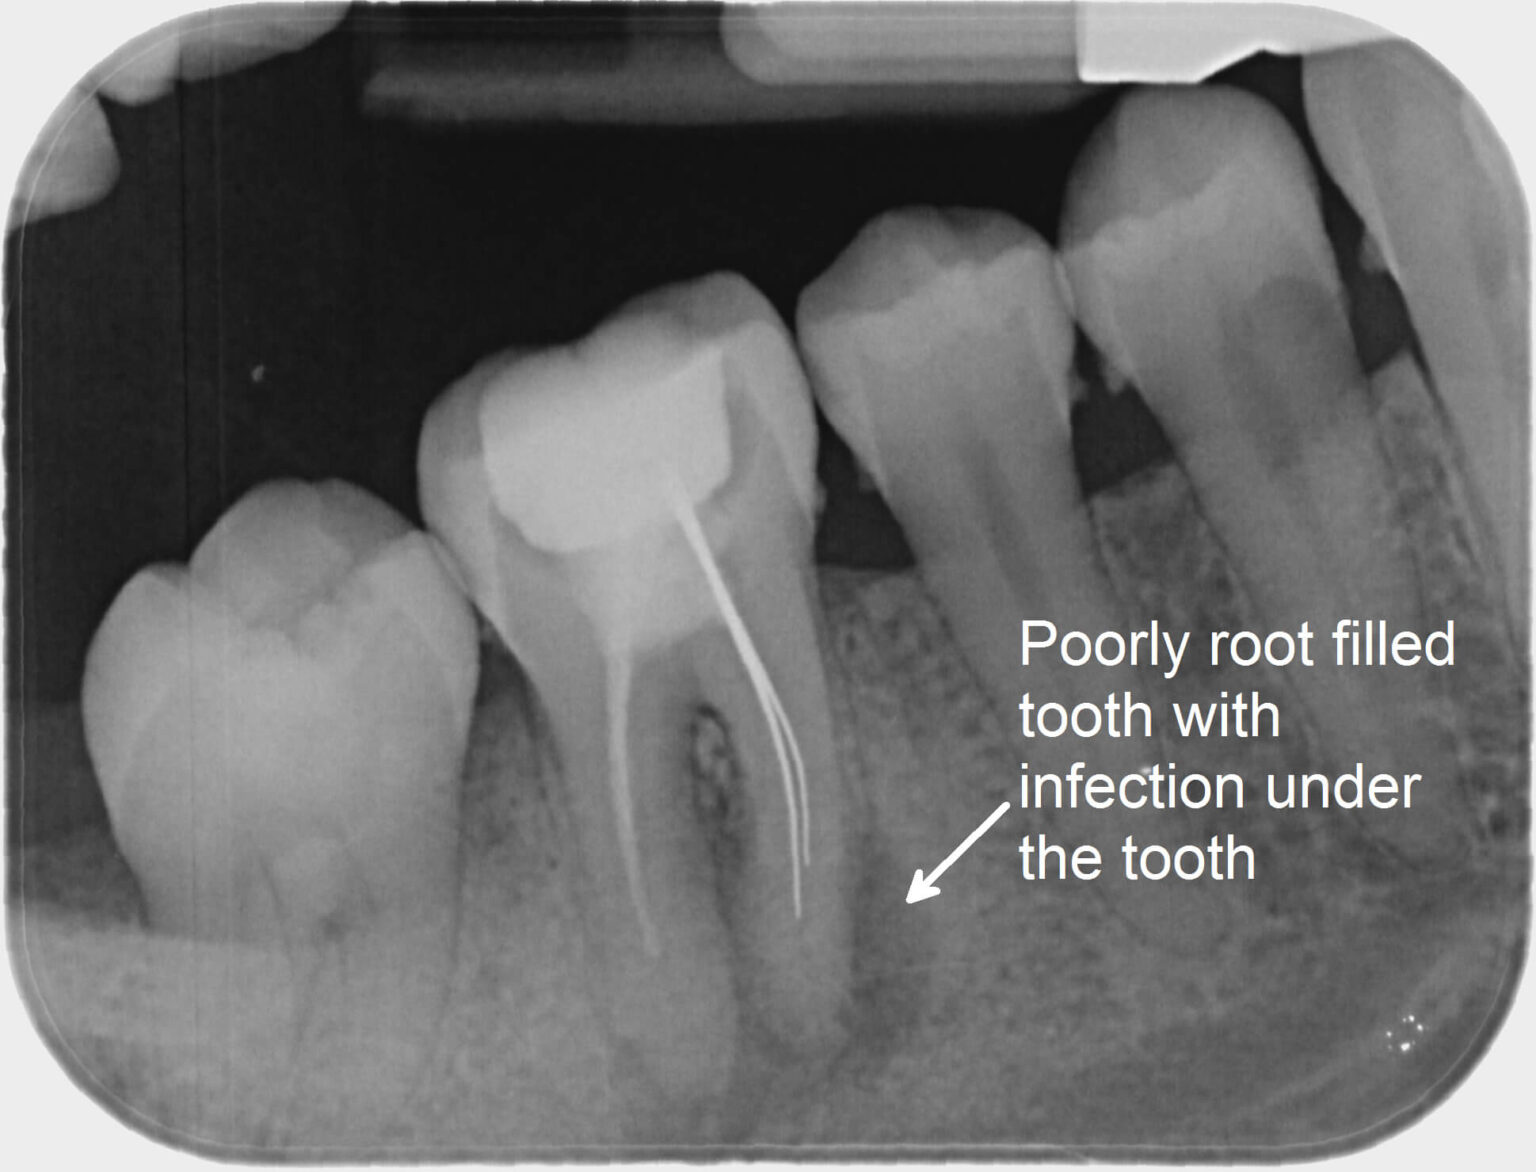

From myholisticdentist.com